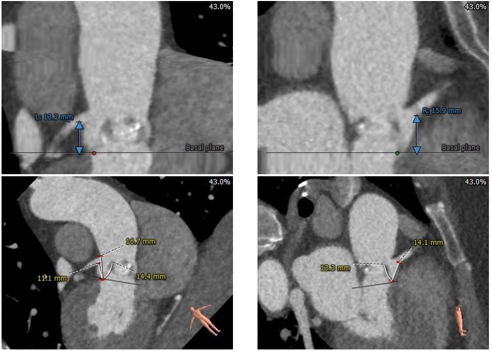

术前CT评估:

主动脉根部:

三叶式主动脉瓣,瓣环直径约22.5mm,LVOT呈收口型STJ、升主动脉内径可,非横位心,瓦氏窦较小。

冠脉测量:

左、右冠脉开口高度尚可,瓣叶长于冠脉开口下缘

钙化测量:

轻度钙化,左、无窦瓣叶纤维融合

入路测量:

股动脉入路可

风险评估:

• 三叶式主动脉瓣,瓣叶增厚,轻度钙化,收口型LVOT,锚定难度适中,存在瓣膜移位风险